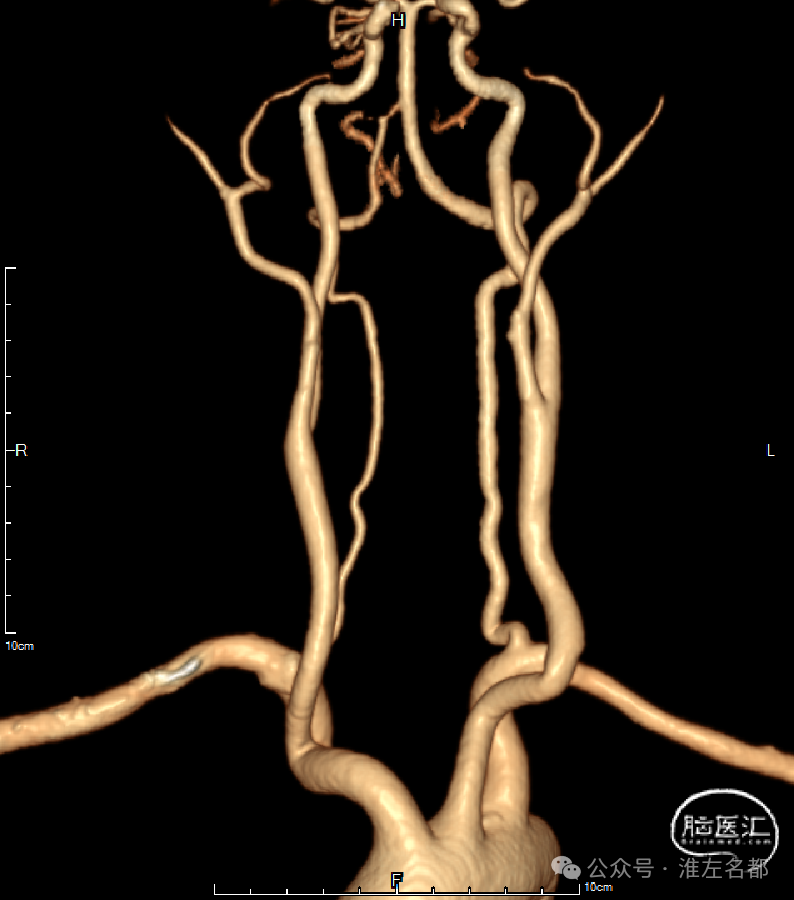

颅脑CTA:右侧大脑前动脉A2段局部管腔严重狭窄,右侧大脑前动脉A1段未发育,左侧大脑前动脉A1段粗大。

颈部CTA:所见脑供血动脉未见明确异常。

首先,患者发病到急诊时间在24小时内,虽然NIHSS只有3分,属轻型卒中。但多模式CT之CTA显示右侧大脑前动脉A2段局部严重狭窄,结合病史和症状,考虑此A2狭窄是罪犯血管病变,故临床给予强化抗动脉粥样硬化治疗,包括:双抗和强化他汀。

其次,由于已知患者此次发病由颅内动脉粥样硬化狭窄所致,当到院后24小时内症状明显加重时,故考虑可能是右侧A2狭窄闭塞所致,再次多模式CT表明原右侧A2狭窄处确实闭塞了,伴其供血区明显低灌注,但核心梗死不明显。右侧A2闭塞考虑原因是狭窄处急性血栓形成。此时,综合病情和多模式CT结果的动态变化情况,为阻止病情进展,挽救危险低灌注脑组织,实施紧急血管内介入治疗是一合理的选择。